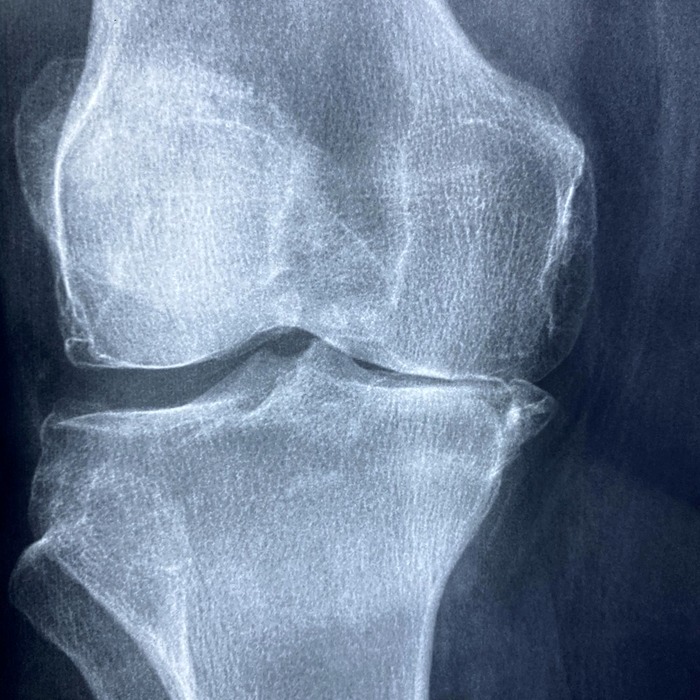

무릎 관절염의 진단에는 여러 가지 방법이 사용되며, 주로 방사선 촬영(X-ray)을 통해 진행됩니다. 방사선 검사는 관절 간격의 좁아짐과 골변형을 확인하는 데 유용합니다.

이를 통해 무릎 관절염의 단계를 평가할 수 있으며, 켈그렌-로렌스 분류법(KL grade)이 일반적으로 사용됩니다.